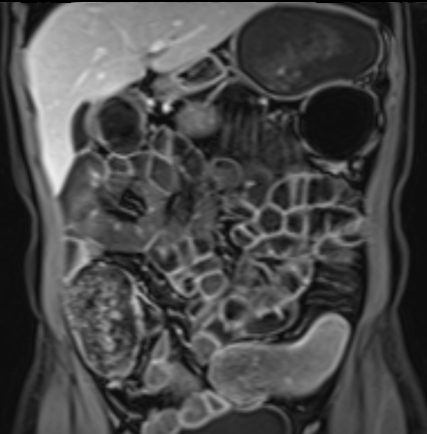

Bệnh nhân nữ 48 tuổi, đang điều trị bằng thuốc kháng TNF, được chỉ định nội soi đại tràng.

Phát hiện hẹp lòng ruột ở đại tràng sigma, không thể vượt qua được khi nội soi.

MR-enterography được thực hiện để đánh giá mức độ lan rộng của chỗ hẹp.

Cuộn qua các hình ảnh.

Ruột non bình thường, nhưng ghi nhận các đoạn hẹp ở đại tràng xuống và đại tràng ngang.

Cả hai đoạn hẹp đều có thành ruột dày đến 8 mm và ngấm thuốc rõ rệt theo kiểu niêm mạc ở đại tràng xuống và kiểu phân lớp ở đại tràng ngang.

Giãn ruột trước chỗ hẹp được ghi nhận ở cả hai đoạn.

Do các chỗ hẹp này không hiện diện khi nội soi đại tràng trước khi điều trị kháng TNF, nhiều khả năng chúng đã hình thành trong quá trình điều trị.

Do đó, quyết định phẫu thuật cắt đại tràng gần toàn bộ với miệng nối hồi-sigma đã được đưa ra.